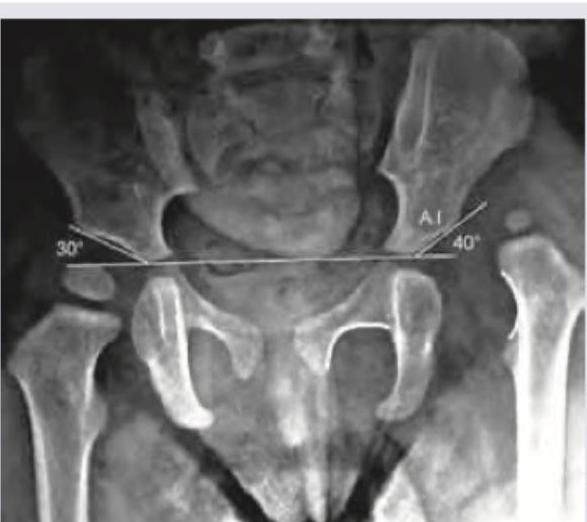

Comment on the diagnosis in the X-ray pelvis of a 2-year-old child as shown below:

Explanation: ***Developmental dysplasia of hip*** - The X-ray shows an **increased acetabular index (AI)**, with the right hip measuring 30 degrees and the left hip measuring 40 degrees. An AI greater than 28 degrees in a 2-year-old child is indicative of developmental dysplasia of the hip (DDH). - The **shallow acetabulum** and **superolateral displacement of the femoral head** (although subtle in this view, suggested by the high AI) are classic radiological signs of DDH. *Perthe's disease* - Perthe's disease, or **Legg-Calvé-Perthes disease**, typically involves **avascular necrosis of the femoral head** in children, usually between 4 and 8 years old. - X-ray findings include **flattening and fragmentation of the femoral head**, increased density, and widening of the joint space, which are not seen here. *TB hip* - **Tuberculosis of the hip** is an infectious condition that would show signs of **osteolysis**, joint space narrowing, and sometimes abscess formation or bone destruction. - These destructive changes and the characteristic age group (Tuberculosis can affect any age group, but focal infections are not typical for this age group) are not consistent with the given X-ray findings. *Slipped capital femoral epiphysis* - **Slipped capital femoral epiphysis (SCFE)** occurs when the **femoral head slips posterior and inferior** relative to the femoral neck through the growth plate. - This condition is typically seen in **adolescents (10-16 years old)**, often overweight, and not in a 2-year-old child. Radiological signs would include a widened or irregular physeal line and posterior displacement of the epiphysis.